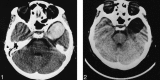

A noncontrast CT shows a well-circumscribed and rounded high-attenuation area in the left Sylvian fissure without clearly defined mass effect. This image depicts a thin crescent of surrounding CSF.fig 2. A noncontrast CT scan obtained 4 years prior to the current admission shows an arachnoid cyst in the left middle cranial fossa, without coexistence of the above-shown hyperattenuating finding